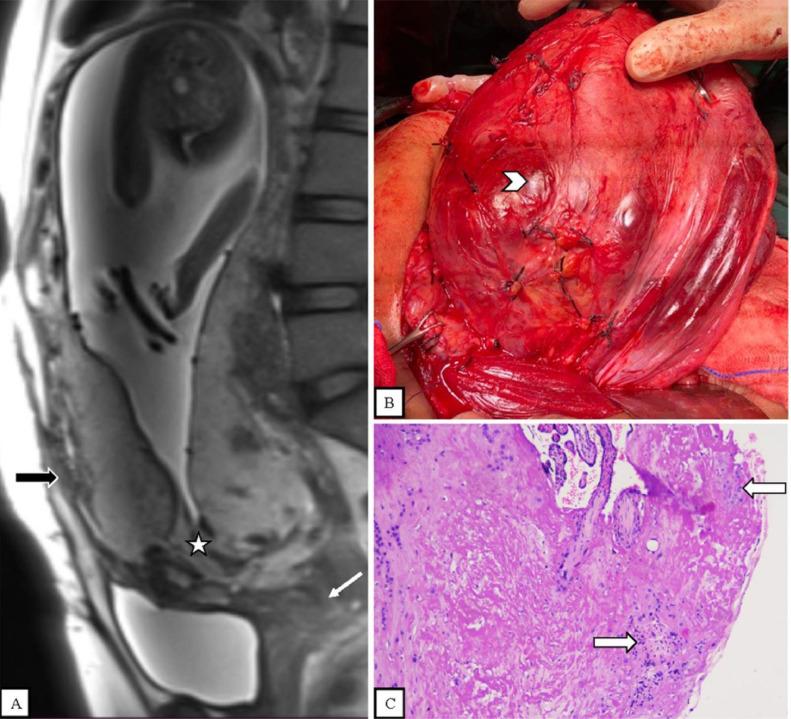

Placenta accreta spectrum (PAS) is defined as abnormal placental adherence or invasion of the myometrium or extrauterine organs. This case series will analyze MRI findings and PAS grading, in addition to emergency situations like massive hematuria and placental invasion with rupture. We report 5 cases of pregnant women with placenta previa with suspected PAS. MRI revealed 1 case of placenta accreta, one case of placenta increta, and 3 cases of placenta percreta. Two cases were emergency situations. All cases were managed with cesarean section. PAS is frequently related to severe obstetric hemorrhage associated with high maternal morbidity and mortality, making diagnosis and management challenging. Ultrasound is the initial diagnostic modality for PAS. Although ultrasound is preferred for PAS diagnosis, MRI provides an effective modality for the analysis of the depth of placental invasion and can be helpful in emergency situations.

胎盘植入谱系疾病(PAS)的定义为胎盘异常附着或侵入子宫肌层或子宫外器官。本病例系列将分析MRI表现及PAS分级,此外还将分析诸如大量血尿和胎盘侵入伴破裂等紧急情况。我们报告5例疑似PAS的前置胎盘孕妇病例。MRI显示1例胎盘粘连、1例胎盘植入和3例胎盘穿透。其中2例为紧急情况。所有病例均行剖宫产术。PAS常与严重产科出血相关,可导致孕产妇高发病率和死亡率,这使得诊断和管理颇具挑战性。超声是PAS的初始诊断方法。尽管超声是PAS诊断的首选方法,但MRI为分析胎盘侵入深度提供了一种有效的方法,且在紧急情况下可能会有所帮助。